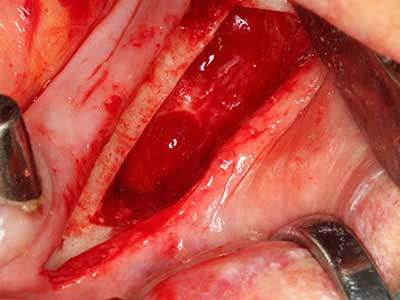

Indication: Sinus lift

Preparation of the lateral window during an external sinus floor elevation is challenging, particularly for implantologists with little surgical experience. Removal of the bone cover of the sinus without injuring the underlying Schneiderian membrane is only part of the operation – after establishing an adequate access, the membranous lining of the sinus must be carefully mobilized to make space for the augmentation materials or the implants. Piezosurgery is useful for this indication in two ways: diamond-coated instruments can be used for selective bone ablation and the underlying mucous membrane remains intact when the procedure is done carefully. The ultrasonic frequencies also enable detachment of the mucous membrane without complications – the frequencies are transmitted into the space between the mucous membrane and sinus floor by special blunt attachments (Cassetta, Ricci et al. 2012, Pereira, Gealh et al. 2014) (Rickert, Vissink et al. 2013). As a result, it is not surprising that current reviews of external sinus floor elevation positively evaluate the use of piezoelectric devices as well as the use of roughened implant surfaces and bone replacement materials (Wallace, Tarnow et al. 2012).